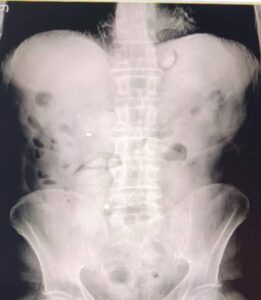

Uşak’ta takside yolcu olarak bulunan İran uyruklu 2 şüphelinin midesinden ve bağırsaklarından 93 kapsül halinde 1 kilo 70 gram metamfetamin...